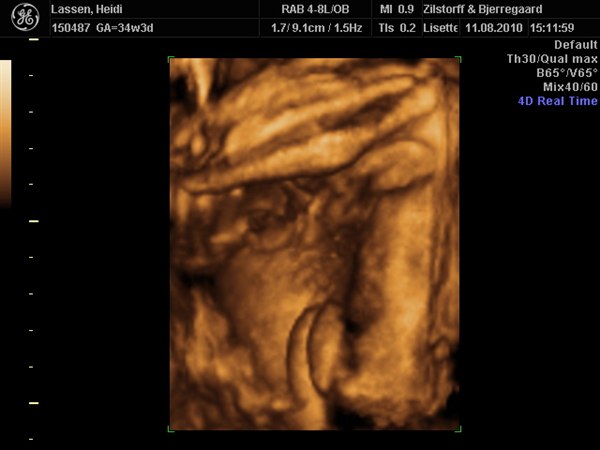

ja på det sidste billede af hende, ligner hun Emil når han blir utilfreds og sådan trækker trutmund/sur mine.

haha nåh ja det er rigtigt.. hun har en lidt sjov mund.. tror det er fordi hendes kinder er så store